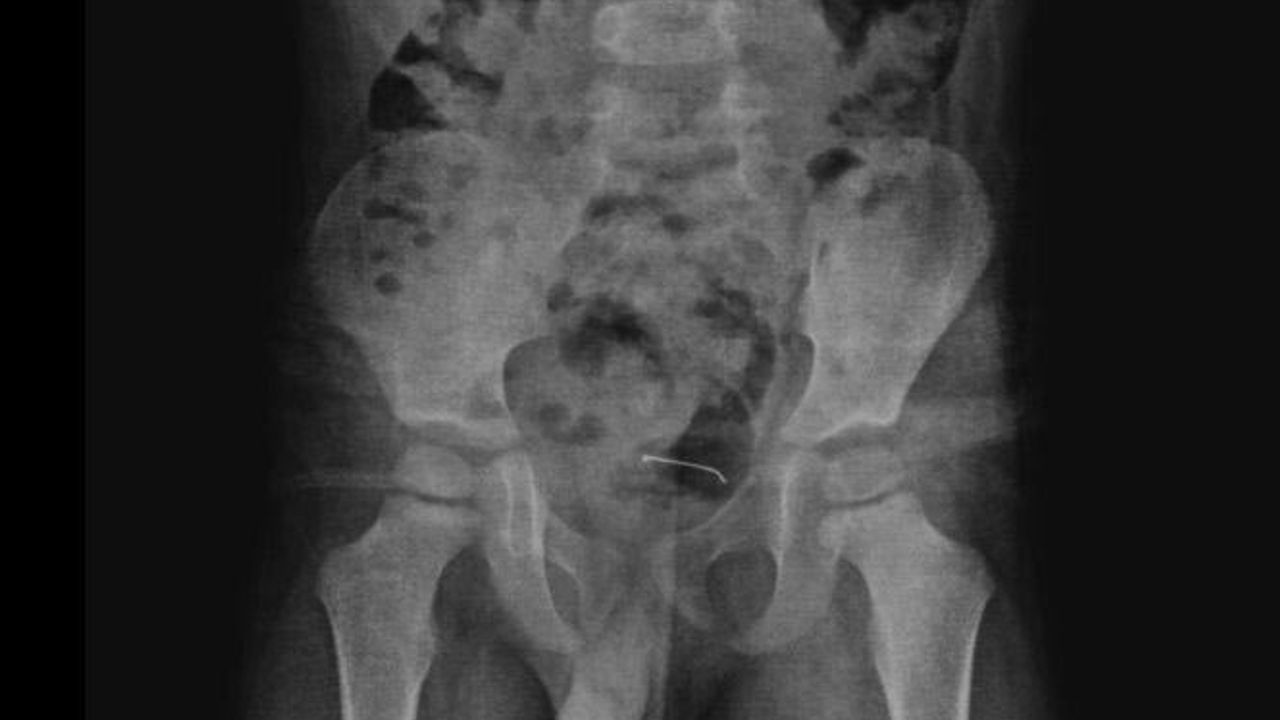

Güroymak'ta sürekli karın ağrısı şikayeti çeken 5 yaşındaki çocuk, ailesi tarafından çeşitli sağlık kuruluşlarına götürüldü. Sonuç alamayan aile, en son Tatvan Devlet Hastanesi'ne başvurdu. Burada çekilen röntgende, çocuğun mesane duvarında metal bir cisim olduğu belirlendi. 9 ay önce yutulan ve vücutta kalan 3 santimetrelik toplu iğnenin mesane duvarına yapıştığı tespit edilince ameliyata karar verildi.

Tatvan Devlet Hastanesi Çocuk Cerrahi Uzmanı Op. Dr. Tahsin Onat Kamçı tarafından gerçekleştirilen operasyonla, toplu iğne başarılı bir şekilde çıkarıldı. Gözlem altında tutulan çocuk, birkaç gün sonra taburcu edildi. Op. Dr. Tahsin Onat Kamçı "Cerrahi operasyonla 3 santimetre civarındaki toplu iğneyi çıkardık. Hastayı birkaç gün takipte tuttuk. Genel sağlık durumu iyi olan hastamızı taburcu ettik. Kesici ve delici cisimler çok tehlikeli. Bu gibi cisimlerin çocukların ulaşabileceği yerlere bırakılmaması gerekiyor" dedi.